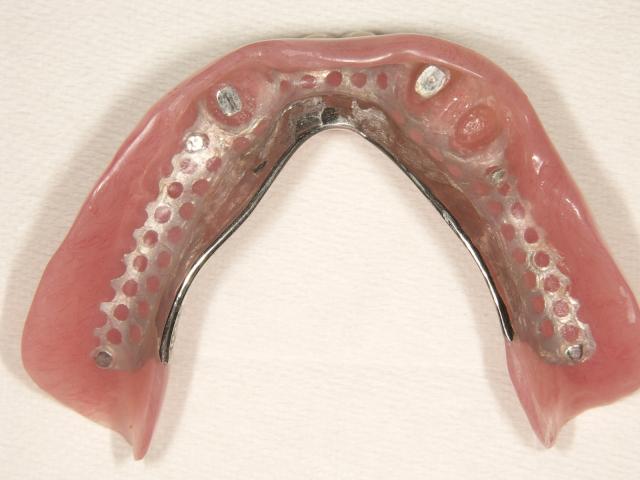

磁石を使用した金属床の入れ歯

2006/09/30

担当:院長

下の総義歯ですが、審美性と機能を考えて磁石を使用した設計で製作しました。

金属床の入れ歯 金属床の入れ歯

金属の針金を使用せずに食べたものも挟まりにくいです!自然感があり良好との事です!